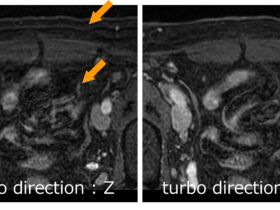

自由呼吸・非同期・非造影MRA『Radial GRE』